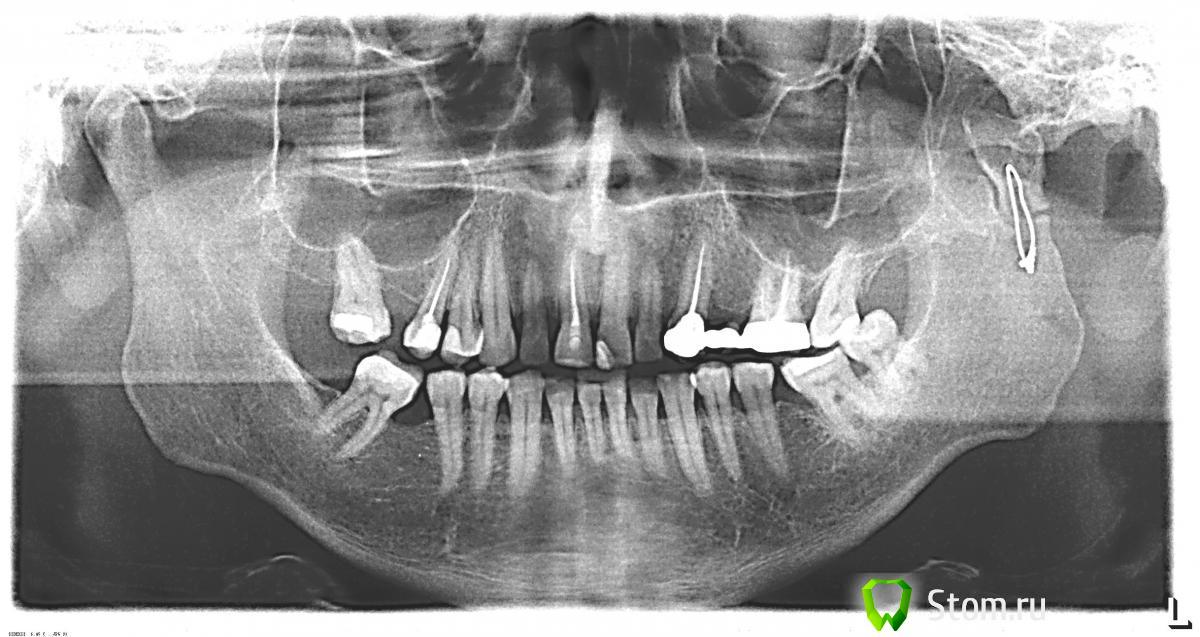

ntdimon Опубликовано 26 января, 2012 Поделиться Опубликовано 26 января, 2012 Здраствуйте доктора и пациенты. Перед новым годом, а точнее 23 декабря у меня случился перелом нижней челюсти. Диагноз был таков: перелом со смещением левого мыщелкового отростка. Смещение отростка произошло во внутрь. 24 декабря мне наложили шины. 28 декабря мне была сделана операция - металлоостеосинтез, вставлена Г-образная пластина. Шины сняли спустя месяц. После процесса снятия шин все зубы ноют, жевать пищу невозможно, но это временно. Перелом сросся судя по снимку хорошо, но смещение прикуса осталось прежним, как и при переломе примерно 5-6 мм в правую сторону. Врач по месту жительства сказала, что предётся привыкать к этому прикусу, т.к. корекцию прикуса должны были сделать хирурги во время операции... Уважаемые доктора в связи с этим возникает вопрос: возможно ли востановить мой прежний прикус, если "Да" то как? И ещё вопрос: в то время когда открываю рот, в месте перелома слышится похрустывание - это страшно или нет. P.S. Совет поциентам: если кто то попал в подобную ситуацию, в первую очередь приобритайте блендер и измельчайте им любую пищу, если пища густая разводите её бульоном из кубиков. Так как организму нужна глюкоза, то самым лучшим десертом к чаю для меня стало сгущённое молоко в пакетах или тюбиках ( очень хорошо вышимать прямо в рот). Ну и на последок, крепитесь, набирайтесь сил, и не падойте духом... Ссылка на комментарий